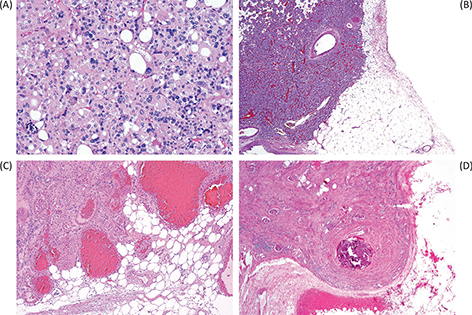

Fig 1

Figure 1. The characteristic gross appearance of oncocytoma (A) varies depending on the size of the tumor, but often has a similar color to normal renal parenchyma (mahogany brown) and characteristically, but not consistently, a central scar. Microscopic appearance typically includes nests dispersed in fibrous stroma (B) and can include tubular structures (C) or densely packed nests (D). Immunohistochemical staining for CK7 can be increased in the central scar area (E) but is typically limited to only scattered cells and small clusters of cells in other areas (F).

Histopathology

The classic histologic appearance of renal oncocytoma includes nests and tubular structures lined by cells with eosinophilic, granular cytoplasm (Figure 1B–D). Uncertainty in the diagnosis can arise when other patterns are present, such as a highly compact nested architecture, resulting in an almost entirely solid appearance, or when small papillary structures protrude into cystic spaces, raising concern of an eosinophilic variant of papillary renal cell carcinoma. Oncocytomas typically contain edematous myxoid or hyalinized stroma, often resulting in at least some areas with nests and tubular structures dispersed in this stroma. Clear cytoplasm may also be focally present, typically in the area of the central scar.